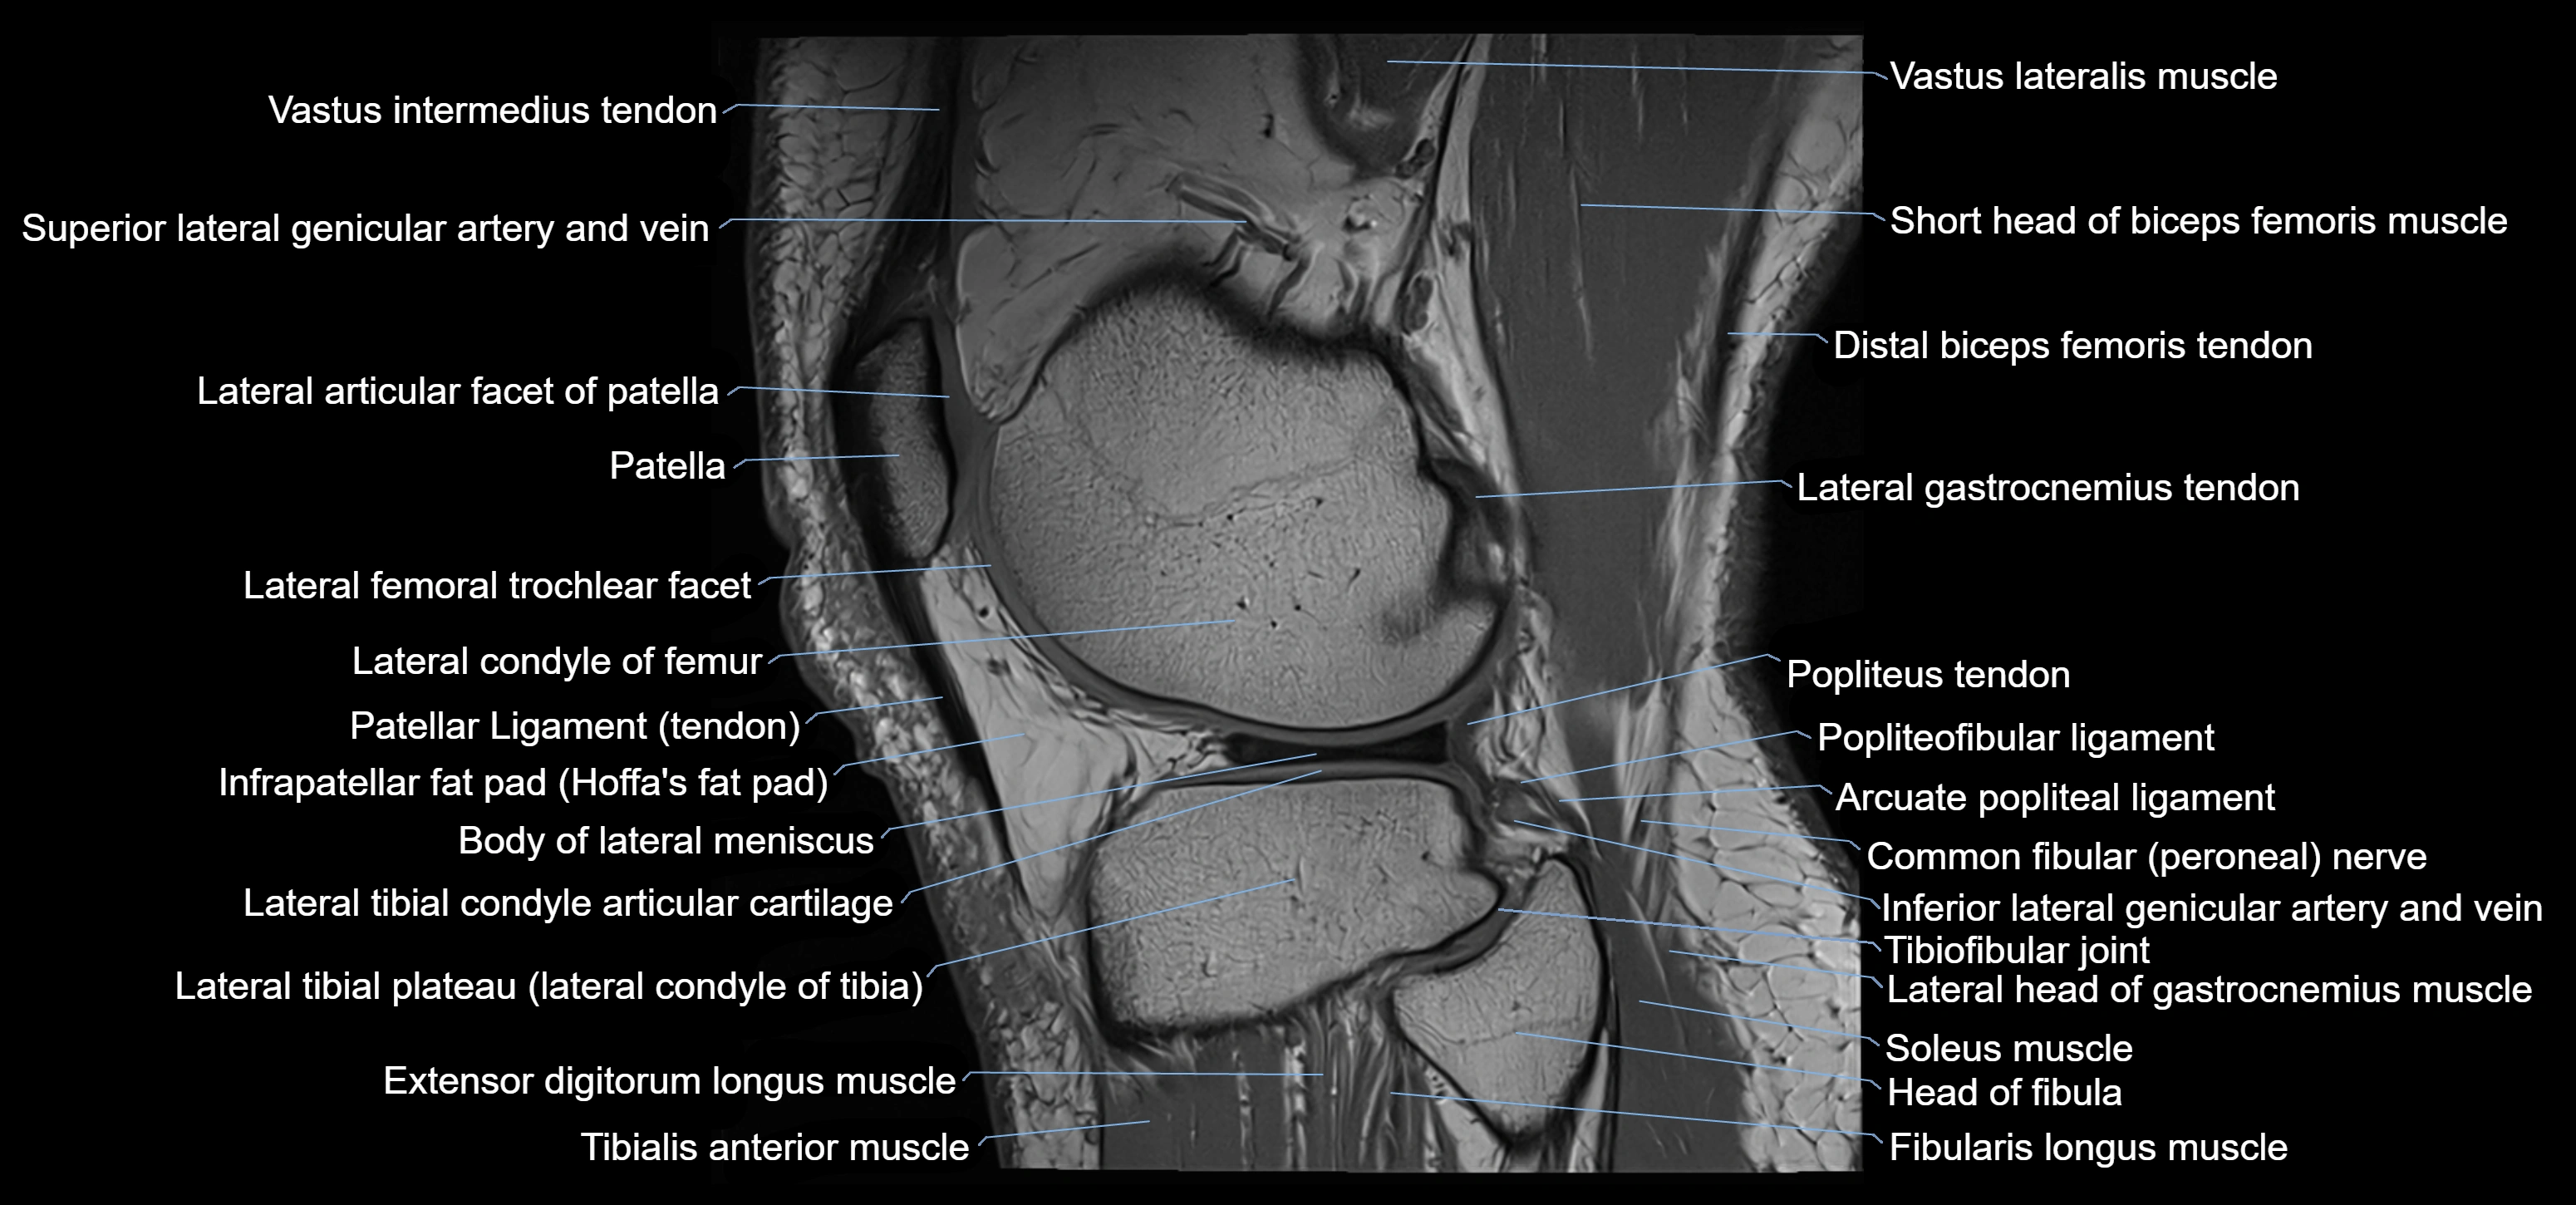

- Body of lateral meniscus

- Distal biceps femoris tendon

- Extensor digitorum longus muscle

- Fibularis longus muscle (peroneus longus muscle)

- Head of fibula

- Inferior lateral genicular artery

- Inferior lateral genicular vein

- Lateral articular facet of patella

- Lateral condyle of femur

- Lateral gastrocnemius tendon

- Lateral head of gastrocnemius muscle

- Lateral meniscus

- Lateral tibial plateau

- Popliteus tendon

- Soleus muscle

- Superior tibiofibular joint

- Tibialis anterior muscle

- Tibiofibular joint (proximal)